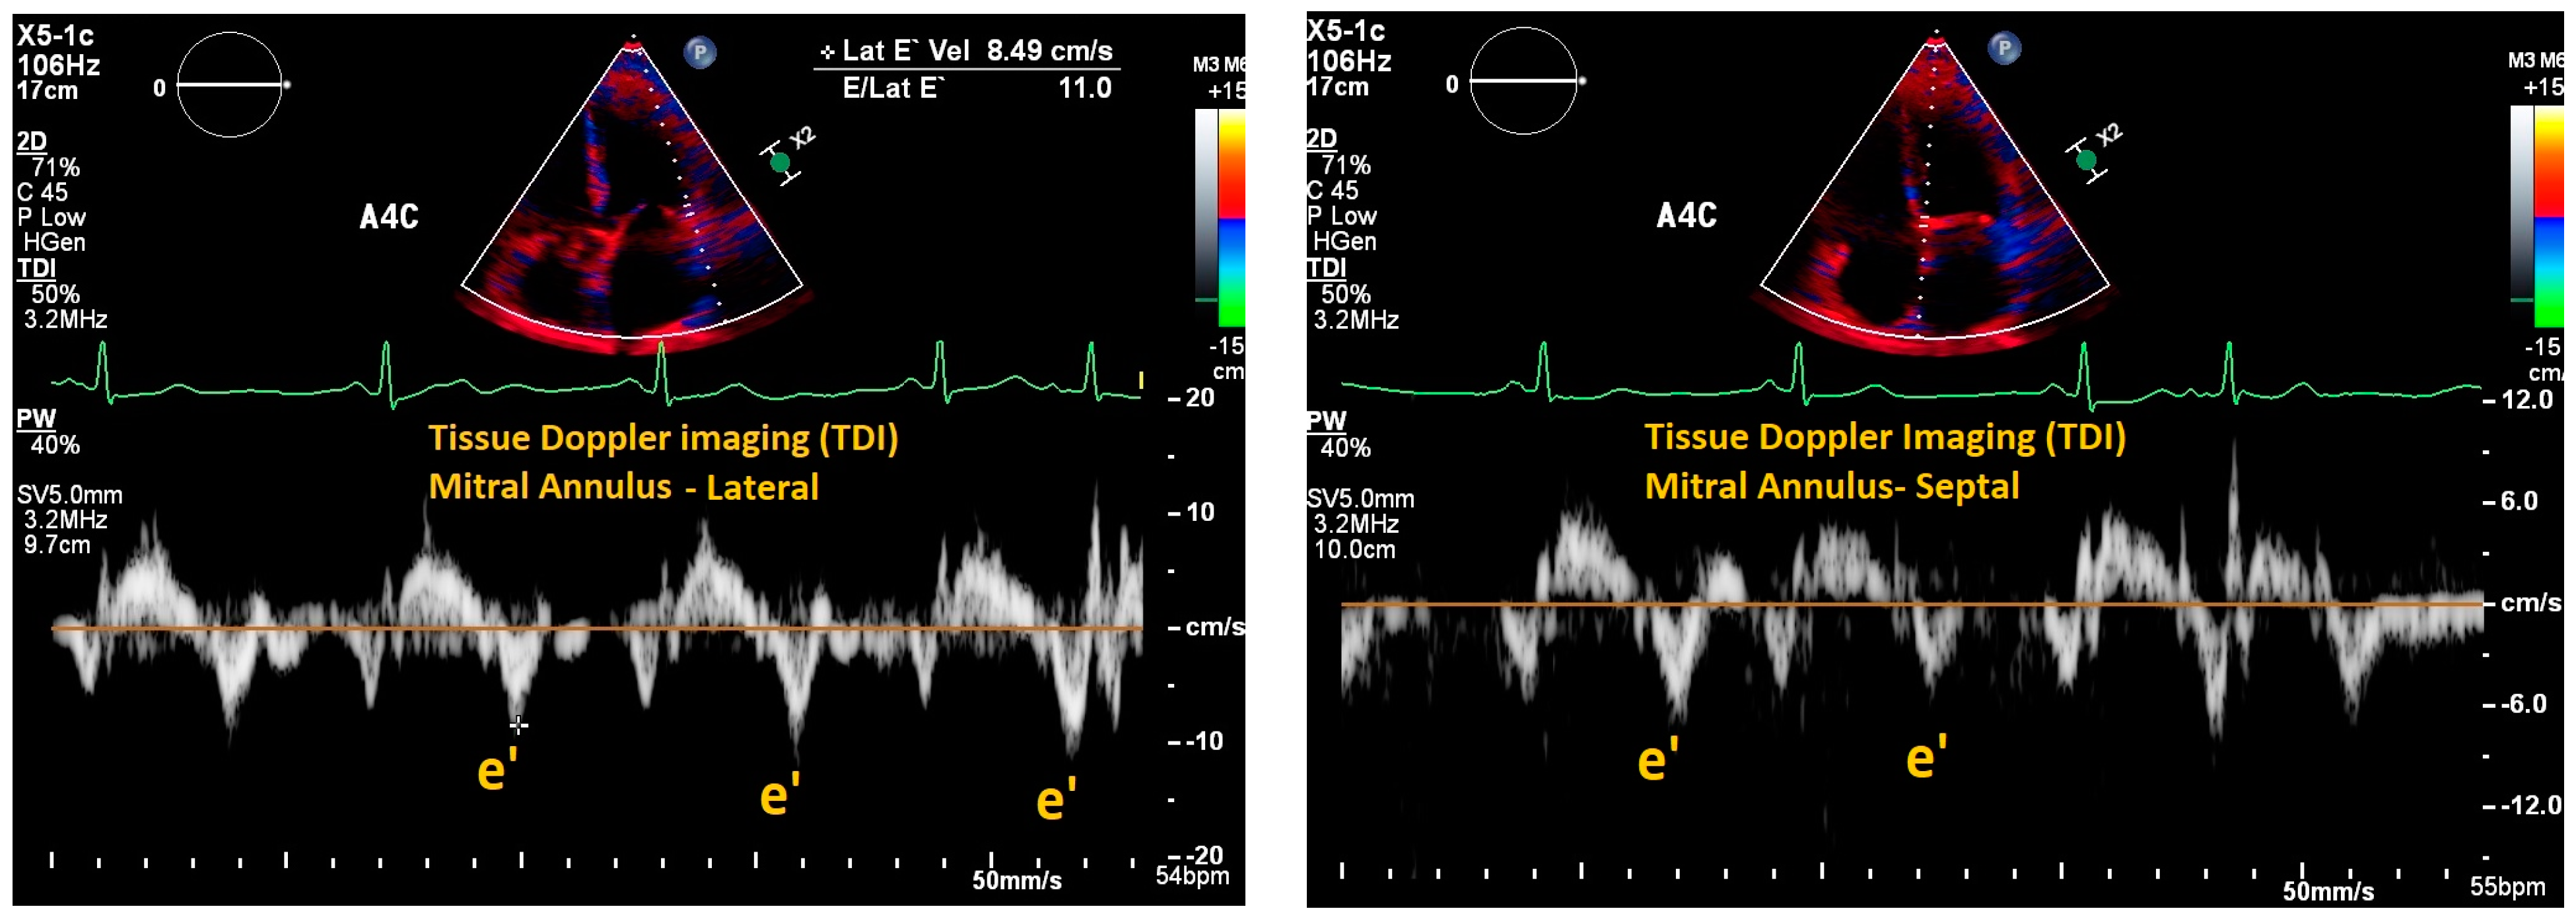

| Mitral E/e’ ratio estimated from the E wave velocity of the mitral inflow Doppler envelope and the tissue Doppler e’ wave velocity at the mitral annulus (septal and/or lateral) | E/e’ ≤ 14 |

|

| |